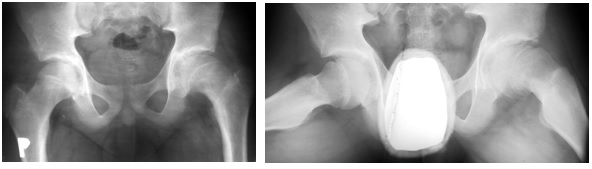

Poniżej przedstawiono radiogram stawów biodrowych w projekcji AP i Lauensteina 11-letniego chłopca, który od 2 dni skarży się na bóle w obrębie lewego stawu biodrowego, trudności w chodzeniu i ograniczenie ruchów. Obraz radiologiczny najbardziej odpowiada :

Pytanie 68